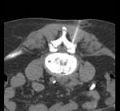

Under computer tomographic or magnetic resonance imaging control, drugs are injected with millimeter precision into the neuralgic points of the spine using fine injection needles. In many patients, this can result in significant pain relief or even freedom from pain. All pain therapy treatments can be carried out on an outpatient basis without any problems due to the low complication rates. A treatment takes a maximum of 10 to 30 minutes.

Periradicular therapy (PRT) is used as a pain therapy procedure for a herniated disc, but also for other back disorders. Here, painkilling and anti-inflammatory drugs are injected with millimeter precision into the painful nerve root under computer or magnetic resonance imaging control. Corticosteroids and long-acting local anesthetics are used. The corticosteroids reduce the swelling of the irritated nerve root, while the local anesthetics reduce the local radiation of pain.